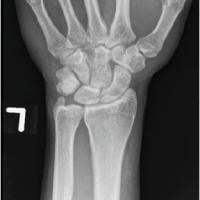

Plain radiographs of the right hand showed soft-tissue swelling (Fig. 3). Given the clinical suspicion, an MRI was performed (Fig. 4), revealing a small lobulated T1 and T2 hypointense subcutaneous soft-tissue lesion in the middle finger at the proximal and middle phalangeal level, extending between the flexor tendon and middle phalanx, measuring approximately 16 × 14 × 10 mm (CC × TR × AP), with surrounding soft-tissue edema. No evidence of bony infiltration was noted. The features were suggestive of a benign soft-tissue lesion (?TGCT). A small focal vascular ectasia was also noted in the index finger, measuring approximately 9 × 5 mm.